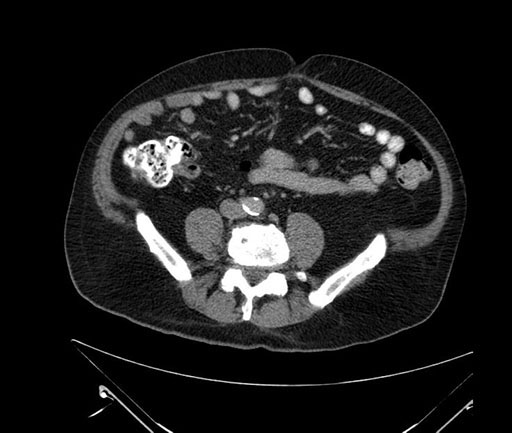

Whipple (pancreaticoduodenectomy) [case 7]

Imaging Analysis

Look through the patient's CT scan to identify any areas of concern for the necessary procedure.

Based on your CT findings, which issue(s) would give reason for "planned slowing down moment(s)" in this case?

Considering a standard Whipple procedure, what step(s) of the operation would you do differently in this case?